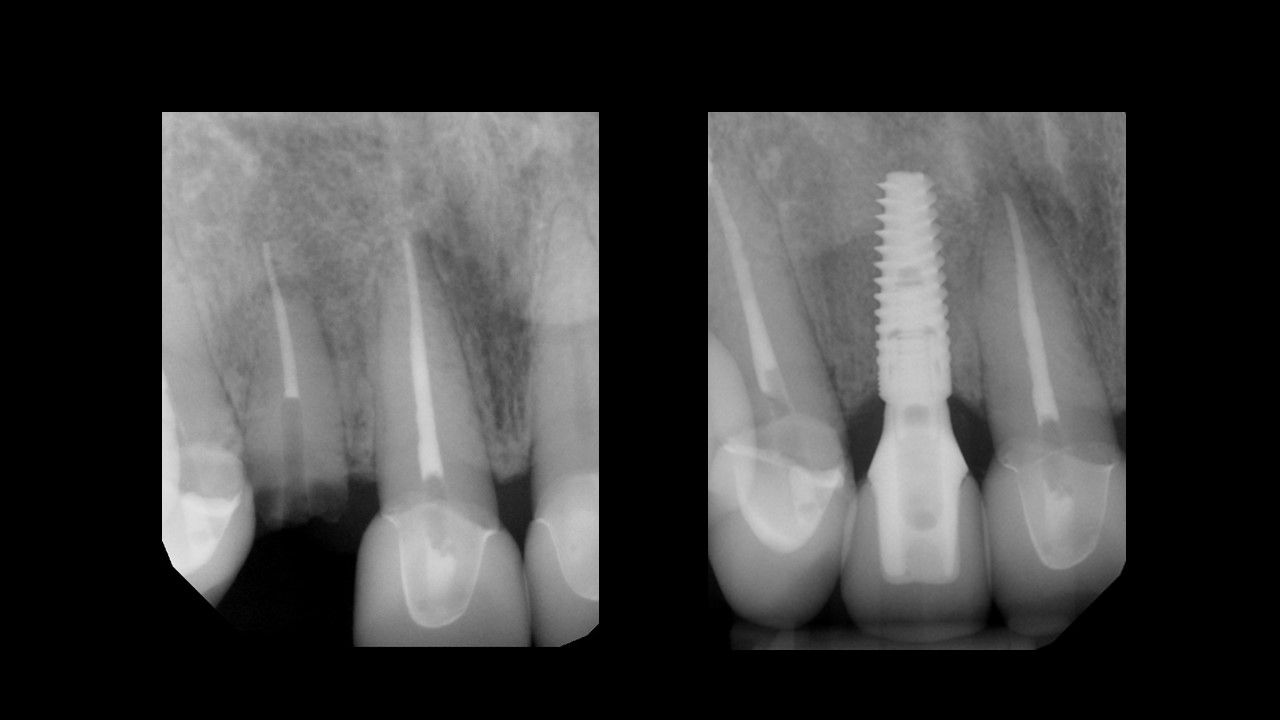

Utilizing procedure-based education1, this level will help the clinician grow into more advanced surgical and prosthetic concepts with the treatment of single tooth anterior implant cases

Throughout this level, the cases will cover topics including: Evaluating buccal and apical bone for immediate placement, Grafting around immediate implants (Dual Zone Technique), Defining implant orientation – The Rules of Six, Assessing primary stability for immediate provisionalization, CAD/CAM abutment options and designs. At the completion of this level, participants will understand how to place and restore a single-tooth implant in the anterior zone. Participants are encouraged to continue their education in Level 4, which will focus on multi-unit cases.